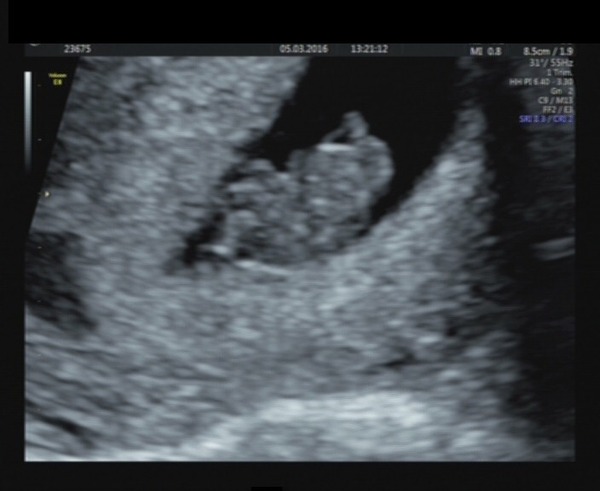

Got the photos emailed through from Saturday's scan, the limb stumps and cord aren't quite as clear as they were on the screen, but it did look less like a prawn than at the 7w scan, and had doubled in size!

Does look a bit like Tintin however....!!Grin